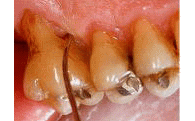

上下大臼歯は、それぞれ3根と2根の複数の根をもっています。

そのため根と根の間の根分岐部において、歯石を除去することは、非常に困難です。

歯磨きも不可能です。それは、右上の図のように、分岐部は、ほら穴のような形態で、器具が入っていかないからです。

実際に抜歯になった上顎大臼歯です。 |